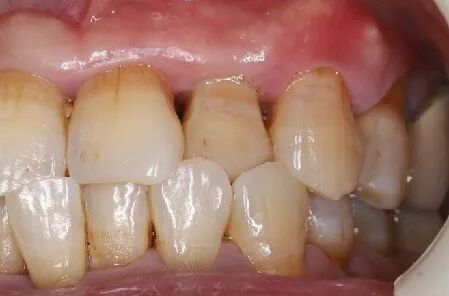

术后8周

牙龈软组织愈合,角化附着龈健康,口腔卫生一般,嘱患者重视日常口腔卫生维护。

术后4.5个月口内照片

术后5个月完成修复

常规印模制取,应患者要求,术后5个月完成修复。